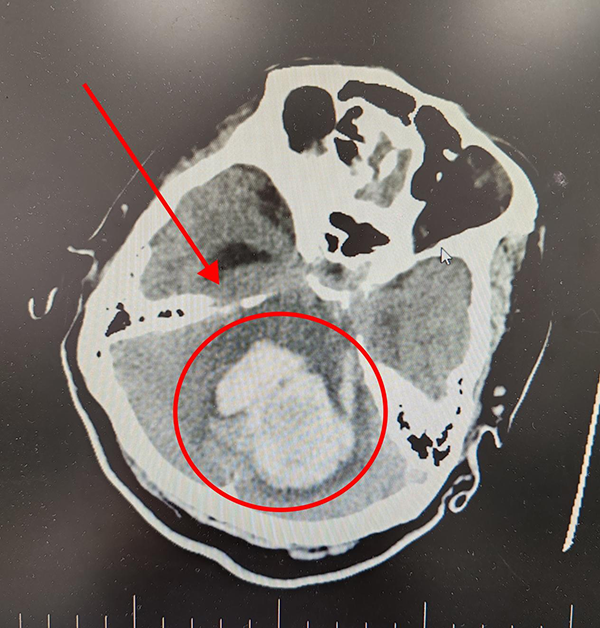

术后患者CT影像 血肿被完全清除

神外二科主任张东强介绍:小脑出血患者病情危重,进展迅速,容易出现神经功能异常,预后差、死亡率高,出血量10ml即有手术指征,出血量超过30ml的死亡率约90%,早期积极干预可降低死亡率,改善预后。近期天气温差变化较大,老年人需注意避免情绪波动,监控好血压,出现不适应立即就医。